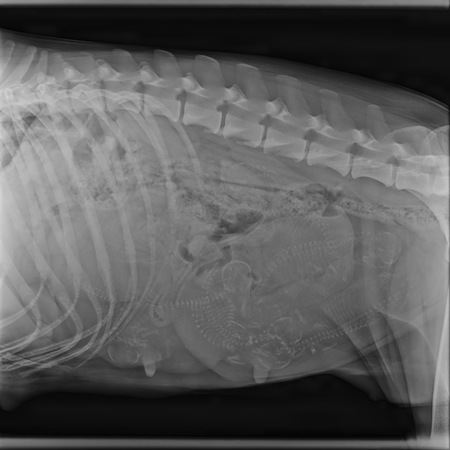

05.02.2026

Heute waren wir beim Röntgen, um zu wissen, ob eines der beiden Extreme - besonders großer oder kleiner Wurf - vorliegt.